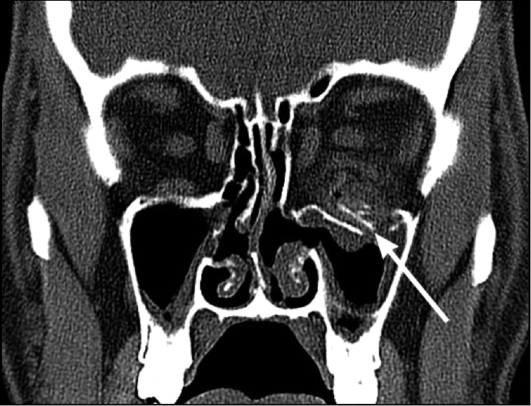

КТ: метод выбора для выявления

рентгеноконтрастных инородных тел (рис. 7).

Рис. 7. Компьютерные томограммы. Инородное тело

правого глазного яблока (стрелка)